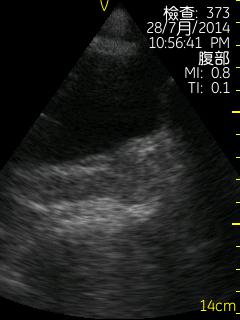

Vscan临床图片 腹部